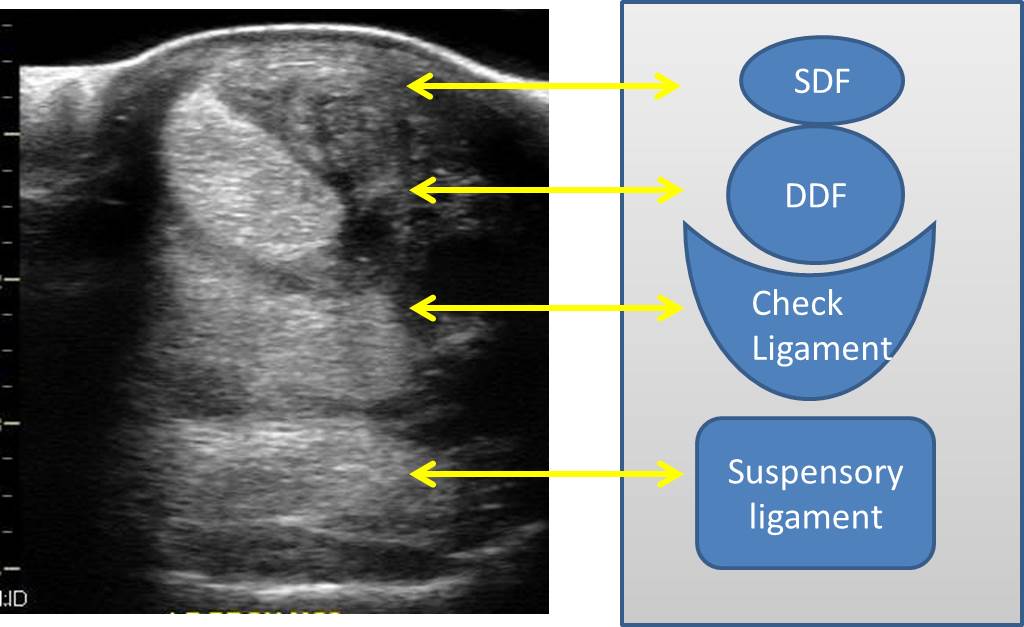

From veteriankey.com

Tendon and ligament physiology Veterian Key Horse Liniment For Tendonitis Equine vaccinationslong live the horse Type liniment can help remove the filling so you can more. Ideally, a liniment designed for tendon repair will contain homeostatic (stop bleeding), anti. Prevents liniment from drying out your horse’s skin due to its soothing and moisturizing properties. Trainers recommend beginning with the legs to avoid shocking the horse with a major temperature change. Horse Liniment For Tendonitis.

From michaelporterdvm.blogspot.com

Michael Porter, Equine Veterinarian Superficial Flexor Tendonitis in a Horse Liniment For Tendonitis Yes, he goes out with a large group (more than 10 horses). Sponge the mixture over your horse’s body, starting with the legs and working upward. Trainers recommend beginning with the legs to avoid shocking the horse with a major temperature change on the large muscle groups of the chest and body. Equine vaccinationslong live the horse When using vetericyn. Horse Liniment For Tendonitis.

Michael Porter, Equine Veterinarian Superficial digital Flexor Horse Liniment For Tendonitis Yes, he goes out with a large group (more than 10 horses). Liniments are designed to provide temporary relief for minor aches and pains often associated with arthritis and overworked. Equine vaccinationslong live the horse Type liniment can help remove the filling so you can more. Trainers recommend beginning with the legs to avoid shocking the horse with a major. Horse Liniment For Tendonitis.